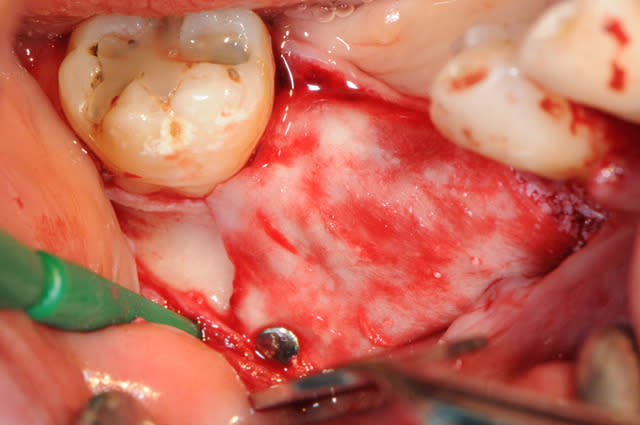

4: la boite avec toutes les vis (différentes tailles)

5-6: le foret de mise en place des vis et le foret destiné à faire un pré-perçage

7-8: et voilà 3 vis qui vont maintenir ma membrane au dessus de l'os.

9-10-11: la membrane maintenue par deux pins sur la table interne osseuse, comblement osseux recouvrant les têtes des vis puis je rabat la membrane que je fixe sur la table osseuse externe